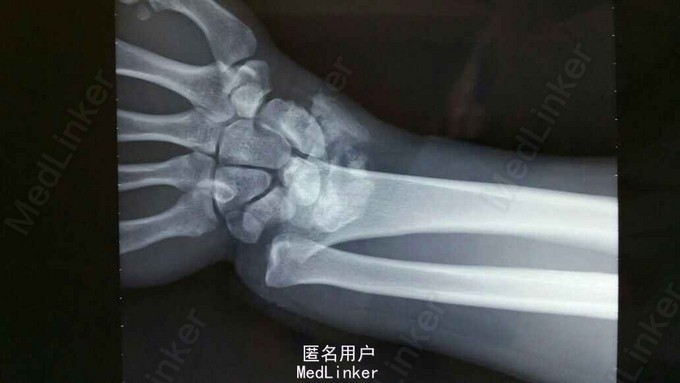

诊断:双尺桡骨远端粉碎性骨折 治疗:入院后,给予手法复位夹板固定,左手神经症状明显缓解,给予对症治疗,消肿后,于2015年8月27日行手术治疗。

请问大家,对于这种骨折是行外架+克氏针固定好,还是钢板固定好?